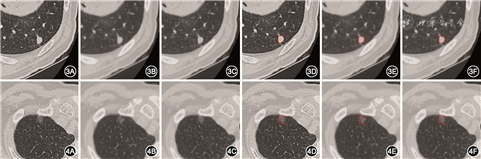

对本研究中入组的1 066个肺结节的测试结果表明,使用本研究所构建的方法,不同重建算法下肺结节的分类准确率差异无统计学意义(P>0.05);不同重建算法下结节分割的Dice系数差异也无统计学意义(P>0.05),模型在不同CT重建算法下表现稳定。肺结节按照不同大小分组的统计结果也表明,模型效果都随着结节的增大而提升,除3 mm以下结节外,其余同一分组在不同重建算法下分割效果稳定,不同重建算法下模型分割出来的实性、亚实性结节的轮廓非常相似(图3、4),维持了较高的一致性,且差异无统计学意义(P>0.05)。此外通过分析不同大小结节下模型的效果,发现分割效果不好的主要集中在直径<3 mm的微结节上,这是由于微结节的尺寸较小,边界不容易确定,导致Dice系数指标易产生偏差,不过随着结节增大,模型的效果不断变好,而偏大的结节临床分析的意义更大,表明模型符合临床的需求。